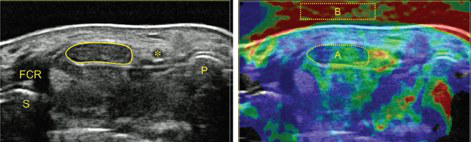

The simultaneous application of structural and functional imaging techniques is described as multiparametric (MP) (Fig. 9). Studies have shown that the MP approach results in greater diagnostic accuracy (Fig. 10).

The use of fusion imaging in uroradiology improves ultrasound lesion-detection rates, shows more reliable size controls at different time points, is an alternative to in-bore biopsies (Fig. 11) and can be used for focal therapy.

- Sonography of carpal tunnel: definition of cut-off values

- Sonoelastography of epicondylitis, plantar fasciitis and Achilles tendon: accuracy in comparison with histology

- Sonographically guided (SG) injections in CTS: sonoelastographic appearance

- SG peripheral nerve injection: sonomorphology

- SG nerve entrapment syndromes in comparison with surgical outcome

- SG injection in sacroiliac joints of children: to prove feasibility

- Dual-energy CT (DECT) in gout: comparison with US, findings in extra-articular regions and cardio in gout and subgroup patients

- X-ray in comparison with DECT in gout patients

- X-ray in comparison with US in erosion assessment

- MRI in comparison with US in tendon overuse assessment

- MRI whole-spine imaging in inflammatory disease: therapeutic follow-up assessment

- MRI sacroiliitis: therapeutic follow-up assessment

- MR tractography (DTI, ADI) in median nerves of healthy volunteers and CTS patients: comparison with sonography.